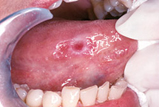

Most of the lumps, bumps, and occasional sores you find in and around your mouth are completely harmless. But you should look out for changes such as white or red patches, ulcers and lumps anywhere in and around your face and neck that persist for more than a couple of weeks. A persistent sore throat or hoarseness is also cause for concern. Most oral cancers are "squamous" (scale-shaped) cell carcinomas. The sides of the tongue are the most common sites for these small lesions. Because the tongue has a rich blood supply and a direct connection to the lymphatic system (a part of our immune system), it's a site from which cancer can easily spread. The floor of the mouth under the tongue is the second most common site. Cancerous lesions on the lower lip, which are usually preceded by chronic sun exposure, are not uncommon.

Regular screening for oral cancer is one of the most important services provided at a dental office. A regular dental checkup includes a visual and tactile (touch) examination for any signs of oral cancer or precancerous lesions in and around your mouth and throat. Anything that looks suspicious, may be analyzed with a routine procedure called a biopsy, in which a small amount of the suspicious tissue is sent to a laboratory for microscopic inspection. This is the best way to get a definitive diagnosis. Should the lesion turn out to be cancerous, the rest of the malignant tissue will be removed. It's possible that radiation and/or chemotherapy will be needed to eradicate the disease. As mentioned before, when treatment occurs early, the survival rates are excellent.